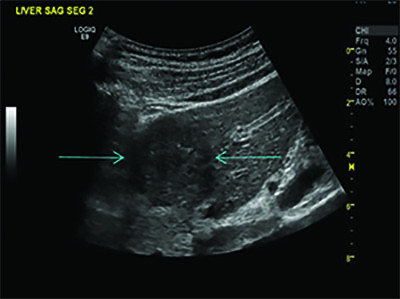

Microbubbles have also shown the ability to noninvasively predict portal hypertension, a condition in which blood pressure is too high in the vein that carries blood to the liver. Early diagnosis of portal hypertension is difficult, as symptoms rarely become apparent until the later stages of liver disease.

In a 2013 Radiology study of 45 patients, SHAPE showed good overall agreement with catheter-based measurements for estimating portal hypertension, especially in patients at increased risk for variceal hemorrhage, a potentially life-threatening effect of the condition. Results of the larger clinical trial also look promising.

1 of 3

“Based on about 135 patients, we have seen 90 to 94 percent accuracy for noninvasively diagnosing portal vein hypertension,” Dr. Forsberg said.